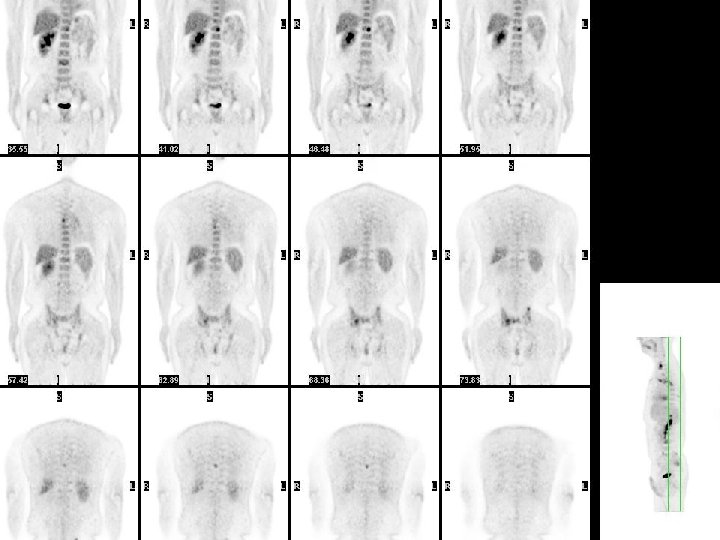

Réalisation technique • • Le patient à jeun et au repos FDG injecté en IV Durée examen # 40 min Acquisition « corps entier » Reconstruction des images Visualisation coupes / 3 plans Corps entier en transparence Calcul éventuel du SUV

Indications • Diagnostic primaire – Dg différentiel masses pulmonaires – Bilan extension lymphomes H et NH, Kc pulm NPC, ORL et VADS , colo-rectaux, , mélanomes • Suivi thérapeutique précoce – lymphomes H et NH • Récidives et métastases – Kc pulmonaire NPC – Kc colo-rectaux – Kc ovaire…. .